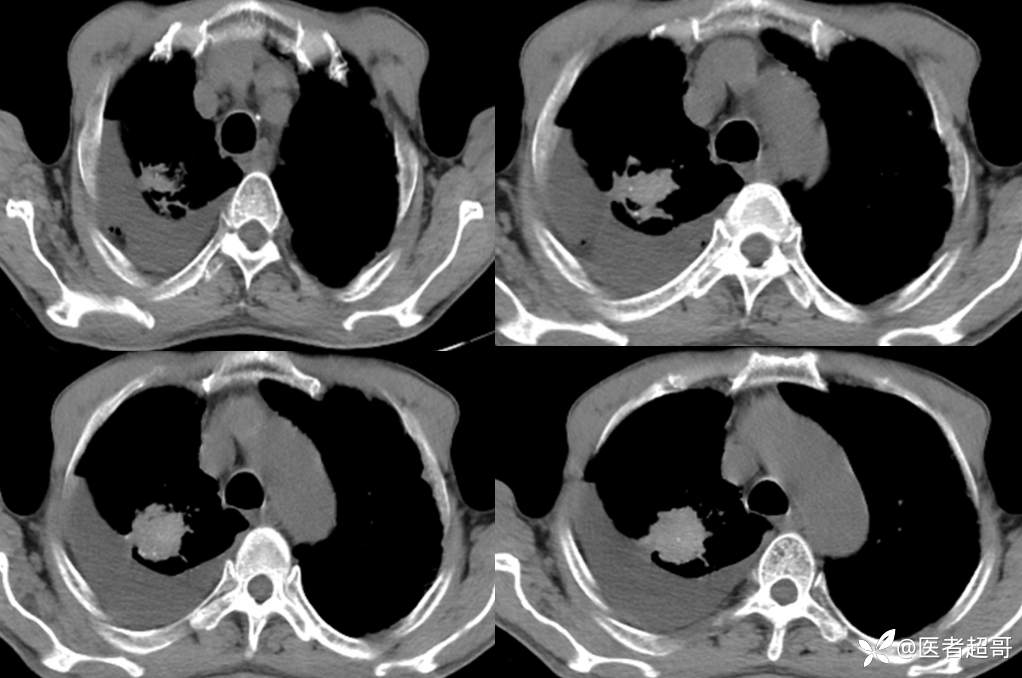

患者,男,72岁,农民,于2021年05月26日17时20分因"发作性精神行为异常10+天"入院。@丁香影像频道